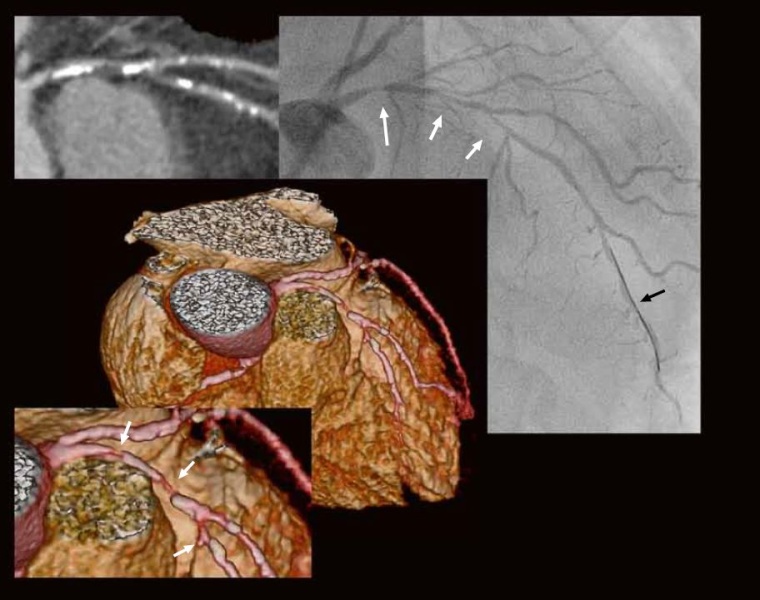

CT -Angiographie:

in der Curved MPR (oben links) schwere kalzifizierte und nicht-kalzifizierte Plaquebildung (Gesamt-Agatston-Score = 884, d. h. hohes Risiko). In der 3D-Rekonstruktion (Mitte und Vergrößerung unten links) und in der Curved MPR (oben links) dringender V. a. hochgradige serielle LAD-Stenosen (weiße Pfeile) vor und nach dem RD1-Abgang. In der invasiven Koronarangiographie (rechts schon mit liegendem Führungsdraht, schwarzer Pfeil) ebenfalls Darstellung dieser Stenosen im proximalen und mittleren RIVA (weiße Pfeile). Strahlendosis CTA = 1,6 mSv.

Therapie:

Revaskularisation des RIVA mit PTCA und Stent-Implantation in den proximalen RIVA. Optimierung des kardiovaskulären Risikoprofils.